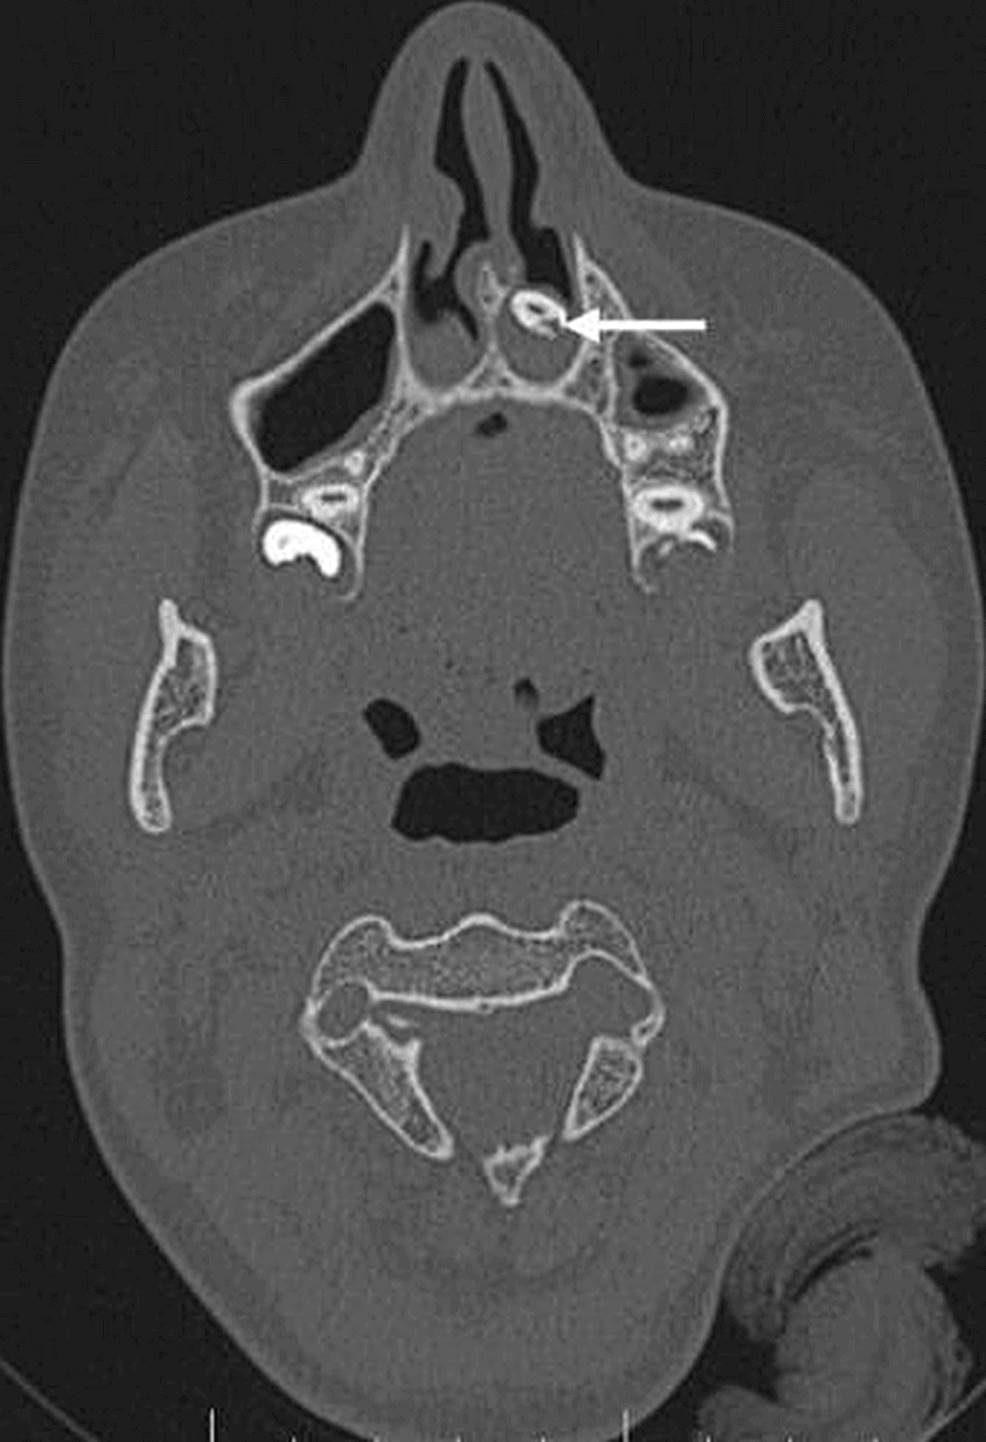

Recientemente, la literatura científica reportó que una paciente de 15 años se presentó con quejas de hiposmia y obstrucción nasal. El caso fue confirmado tras realizársele una tomografía de los senos paranasales y la cavidad nasal mostró una estructura similar a un diente en la cavidad nasal inferior izquierda que se extendía desde el paladar duro.

Raro de diente ectópico intranasal en mujer joven se registra en la literatura  Imagen coronal que muestra una estructura similar a un hueso (flecha blanca) incrustada en el paladar duro que se extiende hacia la cavidad nasal izquierda. Raro de diente ectópico intranasal en mujer joven se registra en la literatura  Tomografía computarizada axial que muestra un diente ectópico en la cavidad nasal izquierda rodeado de tejido blando (flecha blanca). Raro de diente ectópico intranasal en mujer joven se registra en la literatura  La radiografía simple muestra la estructura radiopaca en la fosa nasal izquierda, incrustada en el paladar duro (flecha blanca). Raro de diente ectópico intranasal en mujer joven se registra en la literatura  Imagen sagital que muestra la extensión completa de un diente intranasal (flecha blanca), que se encuentra incrustado en el paladar duro.

Recalcaron además la importancia de las imágenes radiológicas que ayudaron en el diagnóstico de un diente ectópico.